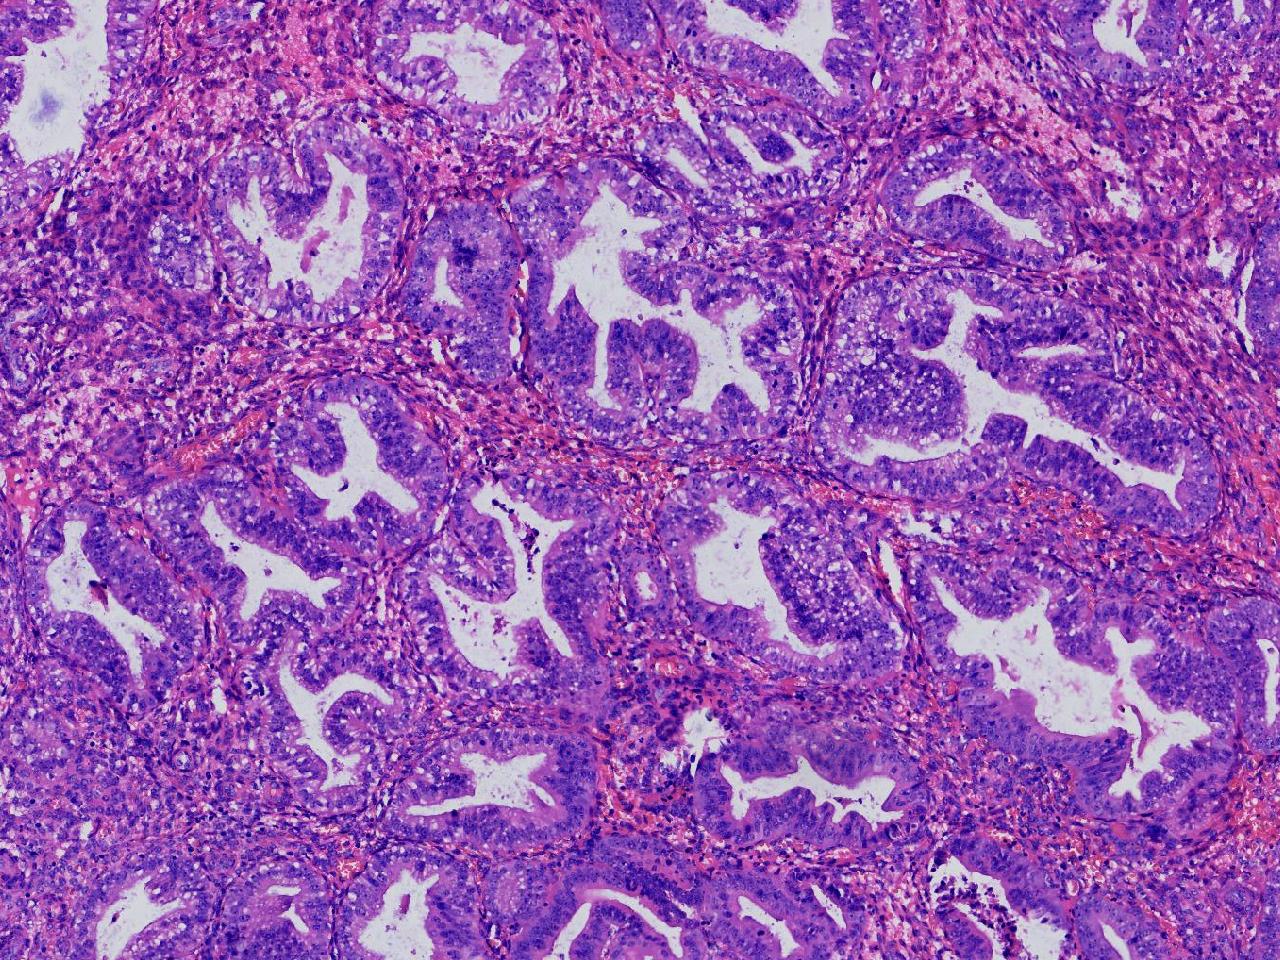

请教诊断.有没有非典?

性别

女

年龄

50岁

女,50岁,彩超示:内膜厚1.3cm。

子宫内膜

灰粉色不整形软组织多块,2X2X1厘米。

无非典型性子宫内膜增生

无非典。